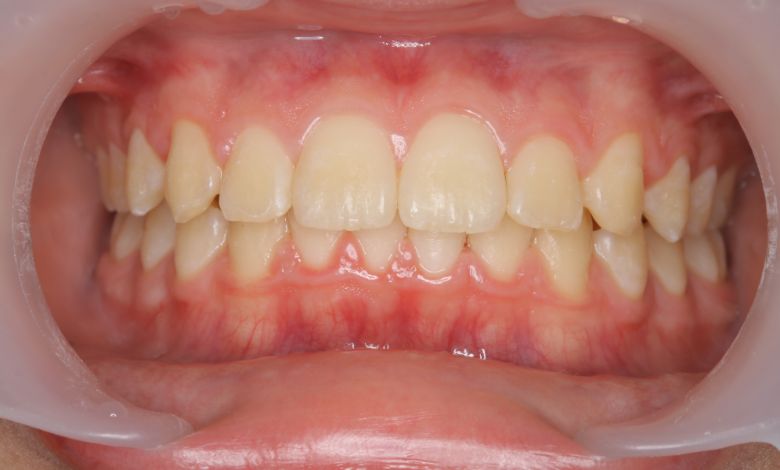

正常な咬合関係が確立され、前歯の自然なアーチと歯軸も整い、歯列全体が滑らかなカーブを描く美しい歯並びに

上下の歯がしっかりと噛み合う、美しい咬合(こうごう)が得られた

精密検査の結果、当院では抜歯を行わず、歯列弓の拡大によってスペースを確保し、非抜歯での矯正治療を選択しました。歯列の叢生(ガタガタ)は解消され、機能的かつ審美的に優れた咬合が得られました。